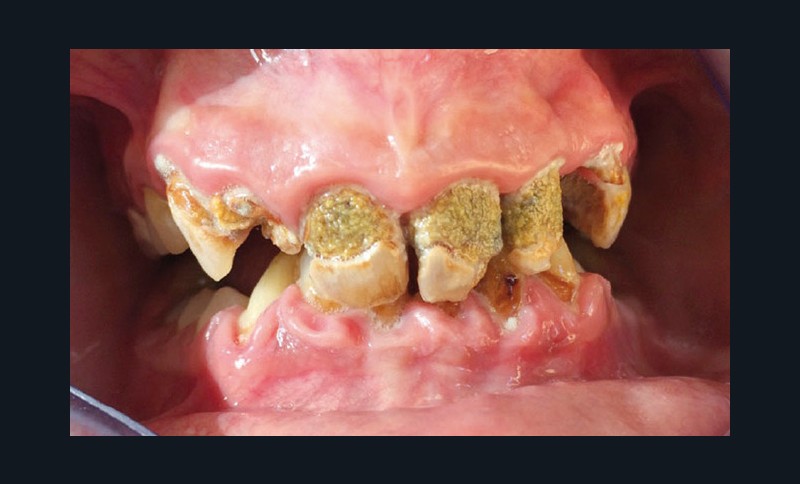

Les spécificités de la santé bucco-dentaire des patients à besoins spécifiques concernent notamment les déficits de l’hygiène buccale, les pathologies oro-faciales, les désordres esthétiques et fonctionnels et une plus grande proportion de pathologies parodontales [5, 6] (fig. 1).

Brown et al [6] ont relevé une prévalence de parodontites de 81 % chez les patients à besoins spécifiques, pour près de 93 % chez les plus de 60 ans et 56 % chez les 20-39 ans. Ils ont également noté une fréquence plus importante de caries et de pertes dentaires. Les difficultés de communication et les inconvénients liés aux différentes situations rencontrées font qu’une prise en charge au fauteuil (soins parodontaux, conservateurs puis restauration prothétique) demeure souvent difficile à mener à bien. Mais l’évolution dans les techniques de sédation, de CFAO, d’implantologie, de collage, est autant d’éléments qui optimisent le temps passé au fauteuil tout en garantissant une qualité de soins à la fois esthétique, fonctionnelle et pérenne à ces patients, même dans des situations « extrêmes » [1].